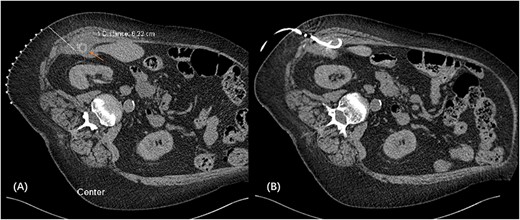

We proceeded with a multiphase computed tomography (CT) scan which was suggestive of a mixed density lesion measuring 62 × 86 × 98 mm arising from the right posterior transverse abdominis/internal oblique muscle, with a well-defined rounded calcific focus at its inferior aspect likely representing a dropped gallstone (GS) associated with abscess formation (Fig. 1). She was commenced on intravenous antibiotics and, in review of her medical comorbidities and DAPT on board, underwent image-guided percutaneous drainage of the gallstone associated abscess collection in the first instance. Following a course of intravenous and oral antibiotics, she was followed up in the outpatient clinic where the drain was removed after 9 days as the output was serous and minimal. Clearance from anaesthetics and cardiology were obtained during pre-operative evaluation of fitness towards surgery, including an ECHO which demonstrated severe left atrial enlargement and moderate mitral stenosis but normal systolic function. DAPT was withhold since initial admission. She underwent an elective procedure 4 weeks later from the initial presentation with pre-operative CT-guided drain localization of the gallstone (Fig. 2) followed by an extra-peritoneal approach of exploration of the right flank. A single 18 × 15 × 14 mm intramuscular gallstone was removed from a deep intramuscular abscess cavity at 6 cm, with fibrous and inflamed tissue surrounding the stone (Fig. 3). Histopathology demonstrated a gallstone with acute inflammation and acellular debris. The postoperative course was uncomplicated with patient discharged on Day 3 post operation and remained well at outpatient follow-up with DAPT restarted.

CT-guided pigtail re-insertion pre-operatively to assist localization of gallstone (A); drain placed in the right subhepatic collection located within the transverse abdominis muscle (B).

Source control must be achieved with stone removal to prevent recurrent abscess or fistula formation. In view of the medically comorbid patient with DAPT on board, we utilized a stepwise, multidisciplinary approach working closely with interventional radiology (IR). Initial sepsis was controlled with antibiotics and IR percutaneous drainage, allowing time for further workup towards delayed definitive surgery with preoperative IR localization (Fig. 2) to precisely track the target and minimize the size of the incision. Staying extraperitoneal with local drainage and evacuation is demonstrated to be safe and effective.